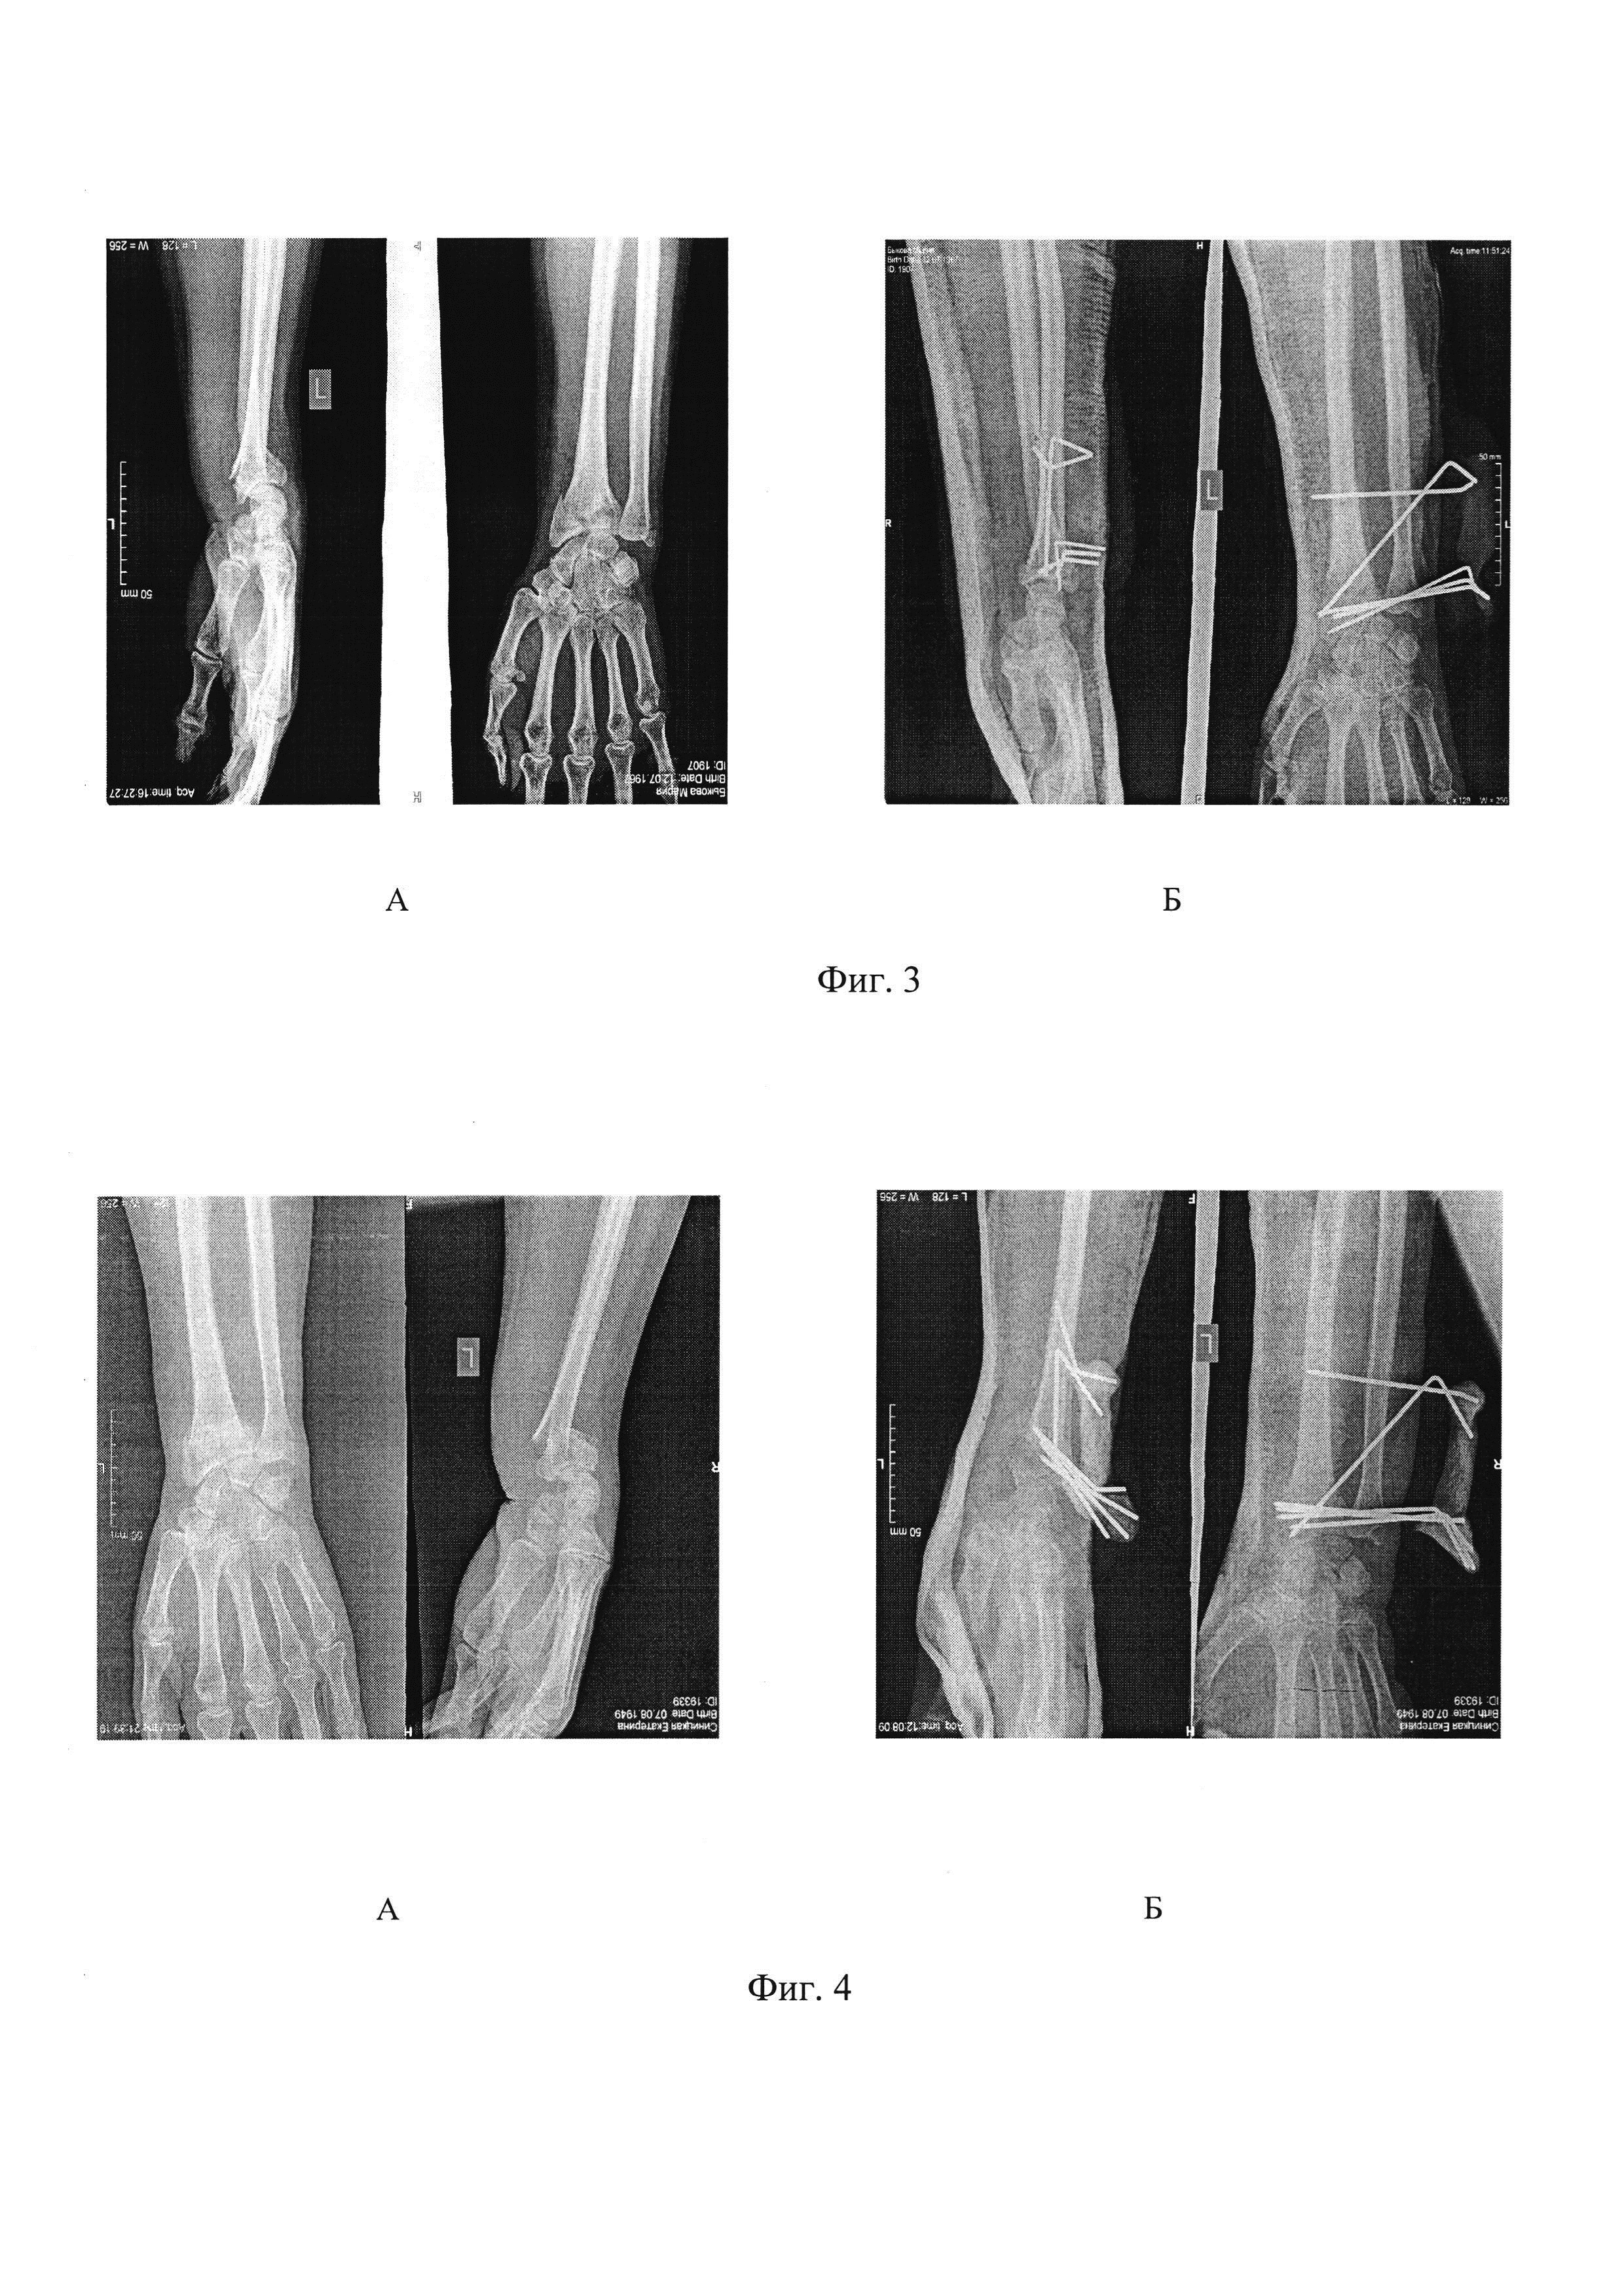

Суть заявленного способа демонстрируют рентгенограммы больных: Фиг. 3. Лечение больного с переломом луча типа «С», а) до операции, б) - после операции.

[14]

Фиг. 4. Лечение больного после вторичного смещения перелома дистального отдела предплечья, а) до операции, б) после операции.